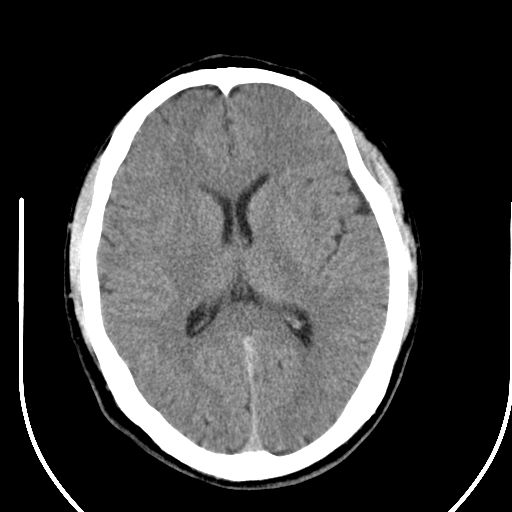

标题: CT25423:头部外伤意外发现右顶叶??? [打印本页]

标题: CT25423:头部外伤意外发现右顶叶???

ct值约13hu。

边缘清晰,没有占位效应,不像脑沟,结合ct值,软化灶可能吧

与脑沟没关系,小软化灶或陈旧性感染吧!

看样年纪不小了直接报腔梗,当然你要想报软化灶也是一样的

考虑右侧额叶巨腔隙灶;建议必要时行mri检查。

软化灶。